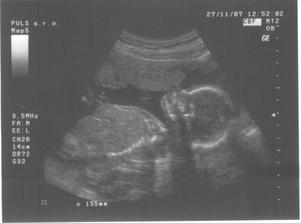

17.8.2007 jsem doma dělala těhu testík a byly 2 //. Poslední kontrola byla 4.9.2007 - 7.tt, velikost miminka 9,6 mm a už bilo srdíčko.Další kontrolu máme 2.10.2007 ... už jsem zvědavá... 2.10.jsem přinesla moč, dostali jsme průkazku a na utz byl vidět pěkný macíček 7,36 cm, čekala jsem o něco málo menší 🙂. Do alba jsem přidala fotečky z utz, ale nejdou popsat - na první - je vidět hlavička, jedna ručička si mne očičko a druhá podpírá hlavičku, okolo tělíčka jsou žebírka, na druhé - je vidět zadeček s nohama křížem ... to je pohodička a na třetí - je celé miminko s nožkama nahoře ..pěkně odpočívá. Jinak bylo vše vpořádku, další kontrola bude 1.11.2007-kontrola, mimís měřil přes 14,5 cm a vážil 189 g. Při kontrole pásl koníčky 🙂. Konečně mi vzali krev asi už na vícero vyšetření najednou. Další návštěvu máme 27.11. ... kontrola byla velmi rychlá, miminek zase pekně pózoval a rozesmíval pana doktora i mě. Chvíli se dívalo nahoru, pak se kokulo na nás z očí do očí. Všechny testy dopadly dobře - triple test i rozbor krve, tak si jen přeju, aby to tak bylo i nadále. Příští kontrolu 3.1.2008 už nebude vidět miminko na ultrazvuku celé, protože už bude moc velké, tak to už se budu dívat jen na jednotlivé části tělíčka 🙂.3.1.2008 byla kontrola ještě rychlejší 🙂, pan doktor zkontroloval srdíčko, jestli ťuká. Při odchodu jsem dostala žádanku na odběry k těhotenské cukrovce, bylo to jen male píchnutí do prstu, s vypitím glukósy v černém čaji. Příští kontrola je 29.1.2008, jsem zvědavá jak dlouho budu ještě moct chodit do práce.Miminko už se má pěkně k světu, už i tatínka kope přes bříško 🙂). Další kontroly probíhaly většinou vpořádku, akorát během února se panu doktorovi zdálo mimi malé, tak jsme čekali jestli doroste, a povedlo se. Doktor t ozdůvodnil tak, že miminka nemusí růst podle průměru, ale podle toho jak se jim chce, což je samozřejmě logické. Nechtěla jsem vedět pohlaví, spíš se těším na překvapení u porodu. Do práce jsem chodila, co to nejdýl šlo, všechno bylo vpořádku. Jen mi při posledním odběru zjistili pozitivní protilátky, tak mi je hlídají a na endokrinologii mi předepsali užívání jodu. Na další kontrolu půjdeme 4.4. do porodnice v Podolí. Kontrol v Podolí bylo ještě několik. V den termínu porodu jsem šla na delší procházku, večer upekla buchty a navařila a ono nic. Poslíčci mě strašili celkem dva týdny, ale vždycky to přešlo. Nakonec jsme museli jít na vyvolání 2.5.2008.